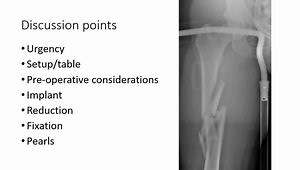

Extraarticular Distal Tibia Fractures OTA 43.A

INTERNAL FIXATOR distal tibia